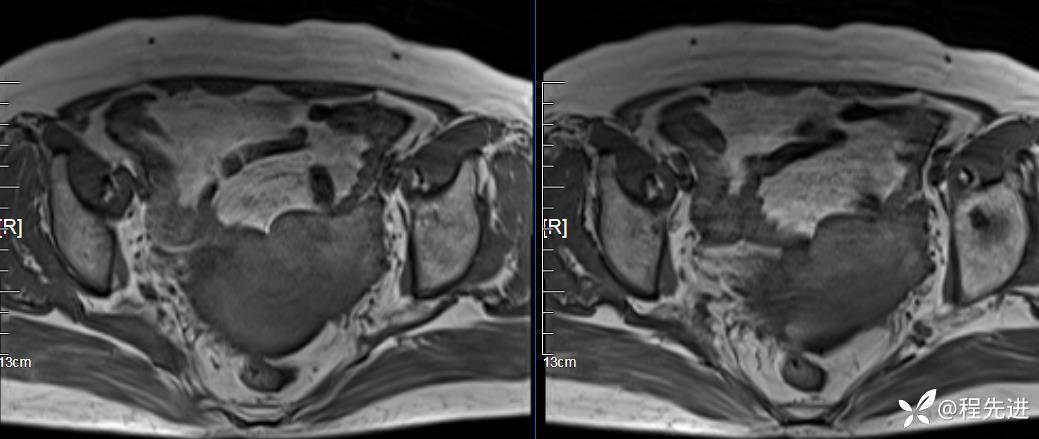

T2压脂: